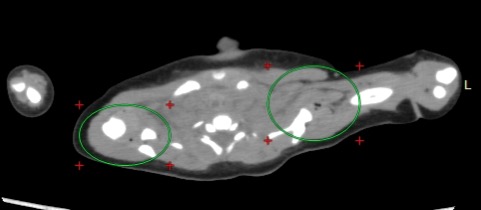

• 両側脛骨近位骨幹端に骨髄針刺入の痕あり。髄腔内に入っていたことがわかる。肩関節、股関節にガスが認められる。

• ※関節内ガスについて ・・・関節内ガスは、牽引や肩を捻じった時にできる。生体の場合、引っ張っている時だけバキ ューム現象は起きる。しかし、戻せば消える。引っ張っていない時にもでるというのは、 長い時間かけてひっぱったか、陰圧が続いている時である。